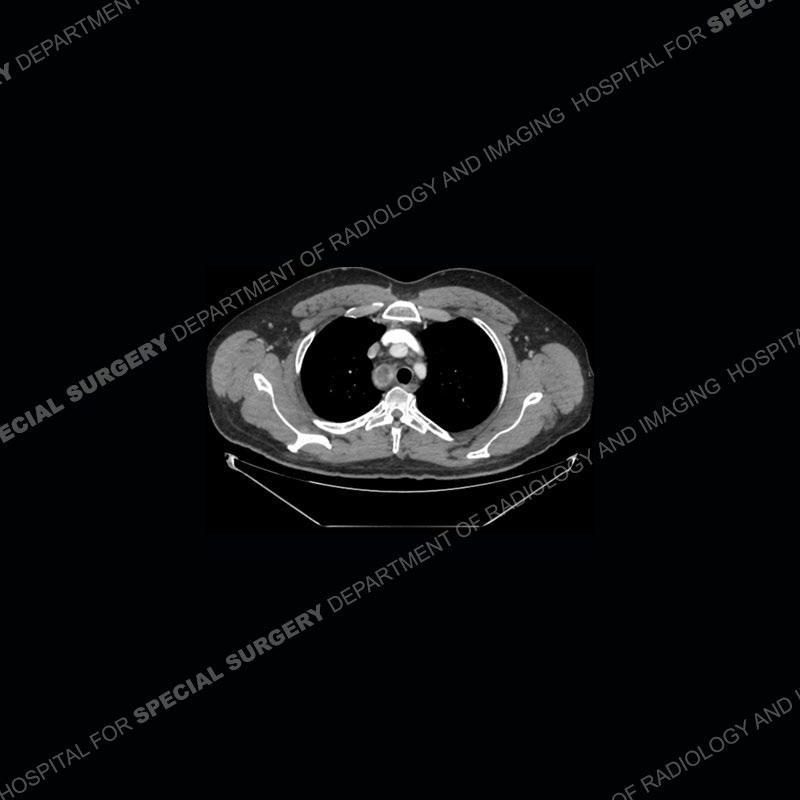

The chest radiographs demonstrate a leftward deviation of the trachea. CT images demonstrate a large, somewhat heterogeneous mass of the thyroid that extends outside the confines of the thyroid tissue. There is a subtle, enhancing soft tissue mass of the proximal right humerus. Slightly prominent mediastinal lymph nodes are present with additionally, multiple supraclavicular lymph nodes.

Over the years we have shown a couple of these cases which may be considered more so an “eye test” then anything else. In clinical practice, these are often very difficult cases as the initial finding of the tracheal deviation may be easily overlooked. Screening radiographs are clearly most often used to assess cardiopulmonary function before induction of anesthesia but at times other findings of great and unfortunately grave consequence can be found. The evaluation of the incidental thyroid mass on CT and MRI is an ever changing situation. Parameters such as age of patient, extension outside of the thyroid, enhancing nodules, and local invasion of lymph nodes are evaluated to see if a lesion needs to be further evaluated.